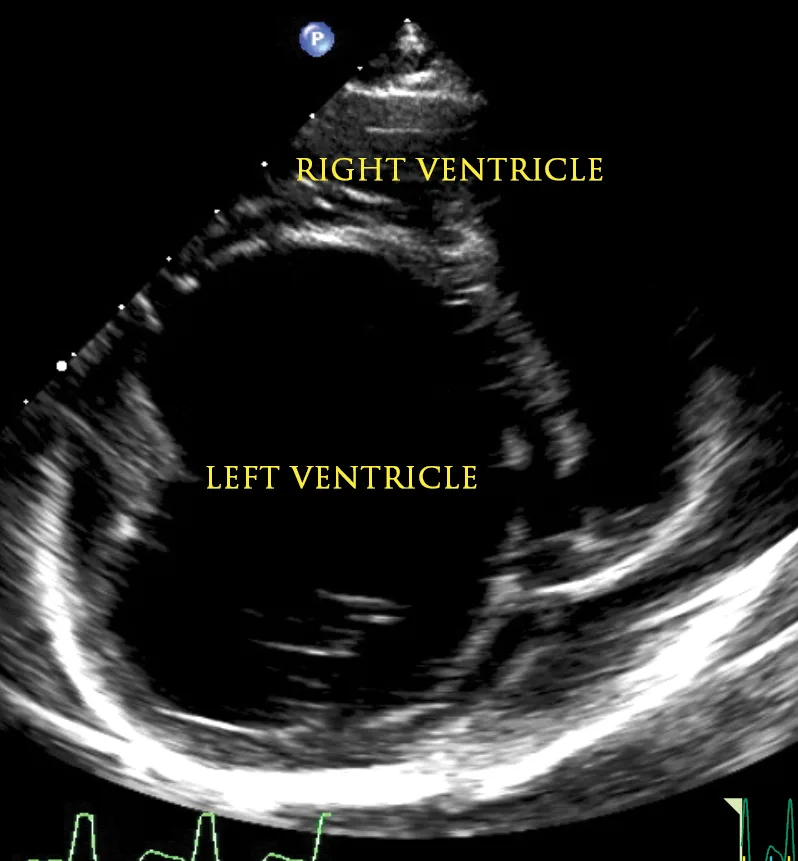

Figure 1

2D echocardiographic image of the left ventricle from the right parasternal short axis view. There is decreased thickness of the LV walls and severe dilation of the LV cavity consistent with DCM.

An echocardiogram and thoracic radiographs were obtained. The echocardiogram revealed decreased left ventricular (LV) wall thickness, severe dilation of the LV chamber (ie, eccentric hypertrophy), and severely reduced LV systolic function. Severe left atrial enlargement with a moderate degree of centrally directed left atrioventricular valve regurgitation (suspected functional) was observed. The left atrioventricular valve leaflets appeared normal in thickness with poor coaptation due to annular stretch. In addition, there was mild dilation of the right atrium and ventricle with a mild degree of right atrioventricular valve regurgitation. Results of echocardiography were consistent with dilated cardiomyopathy (DCM; Figures 1-4).2,3